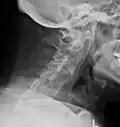

The earliest changes demonstrable by plain X-ray shows erosions and sclerosis in sacroiliac joints. Progression of the erosions leads to widening of the joint space and bony sclerosis. X-ray spine can reveal squaring of vertebrae with bony spur formation called syndesmophyte. This causes the bamboo spine appearance. A drawback of X-ray diagnosis is the signs and symptoms of AS have usually been established as long as 7–10 years prior to X-ray-evident changes occurring on a plain film X-ray, which means a delay of as long as 10 years before adequate therapies can be introduced.[25]

-

Lateral X-ray of the mid back in ankylosing spondylitis -

Lateral X-ray of the neck in ankylosing spondylitis -

X-ray showing bamboo spine in a person with ankylosing spondylitis -